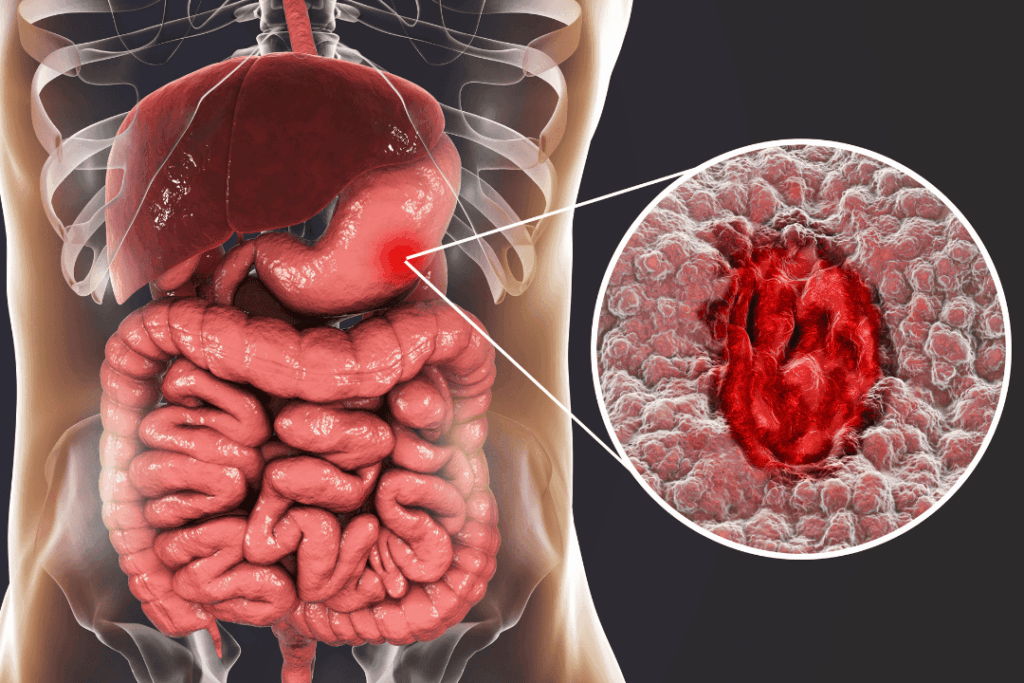

El cáncer gástrico es una de las principales causas de mortalidad en el Perú, y su incidencia sigue creciendo de manera preocupante. Según las proyecciones de la plataforma internacional Globocan, en los últimos cinco años la mortalidad por cáncer en nuestro país se incrementó en un 25 %, y para el año 2025 se estima que se registrarán más de 80 mil nuevos casos y al menos 41 mil muertes por distintos tipos de cáncer.

Dentro de este panorama, la región Huánuco se encuentra entre las más afectadas por el cáncer gástrico, junto con Cusco y Pasco. Las provincias de Leoncio Prado, el distrito del Monzón y la provincia de Huánuco presentan una carga crítica de esta enfermedad.

¿Por qué está aumentando el cáncer gástrico?

De acuerdo con el doctor Mauricio León Rivera, presidente de la Sociedad Peruana de Oncología Quirúrgica, este aumento está vinculado a múltiples factores de riesgo:

El especialista advierte que esta tendencia continuará en ascenso, con un aumento proyectado de hasta 30 % para el 2025.